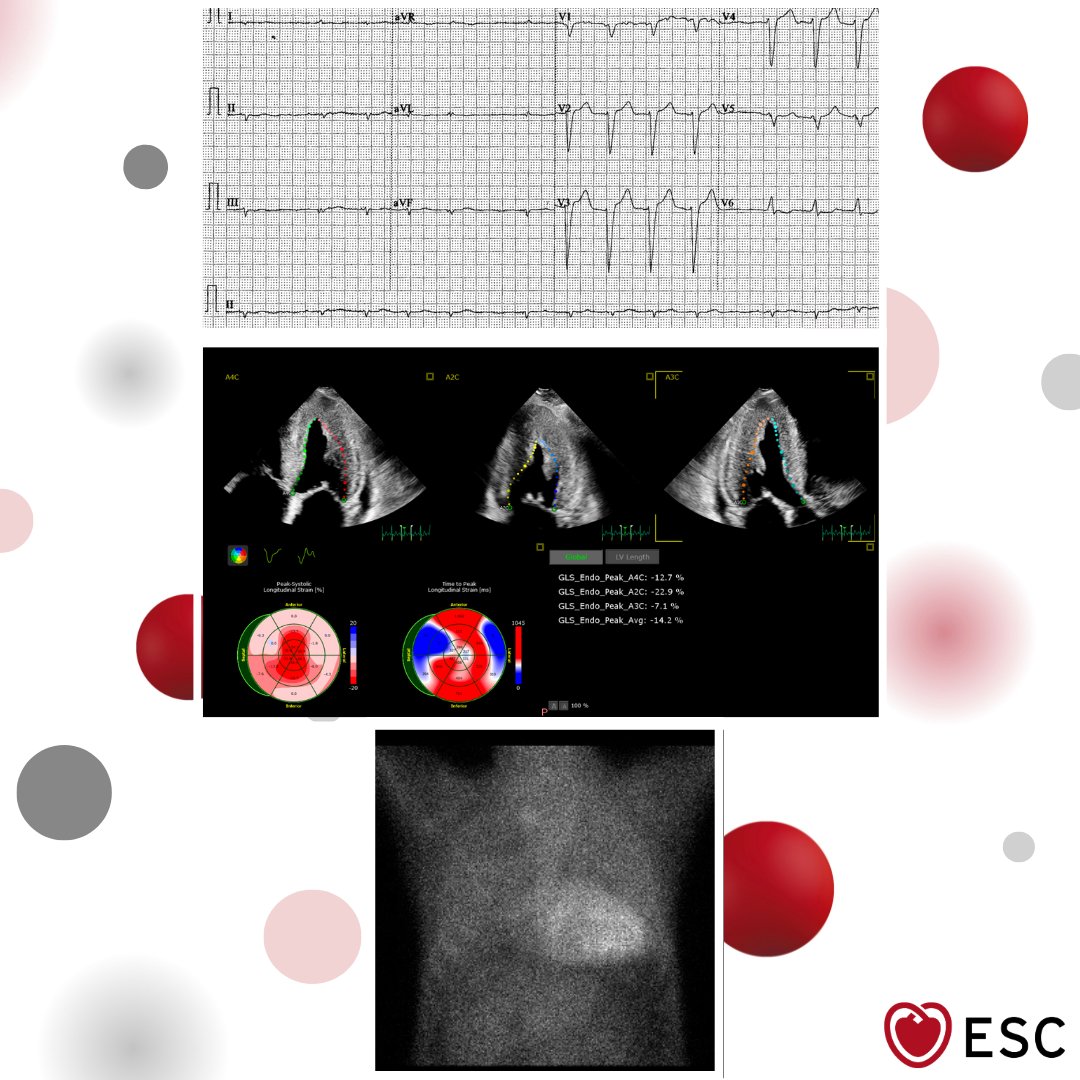

#ImageoftheWeek This #Quiz was submitted by Leila Bigdelu and Ossama Maadarani from the Cardiovascular Medicine Division, Vascular Surgery Research Center, Mashhad University of Medical Sciences, Mashhad, 🇮🇷 ☑️shorturl.at/sdVxi What is your diagnosis? @EACVIPresident

echo_stepbystep's tweet image. #ImageoftheWeek This #Quiz was submitted by Leila Bigdelu and Ossama Maadarani from the Cardiovascular Medicine Division, Vascular Surgery Research Center, Mashhad University of Medical Sciences, Mashhad, 🇮🇷

☑️shorturl.at/sdVxi

What is your diagnosis?